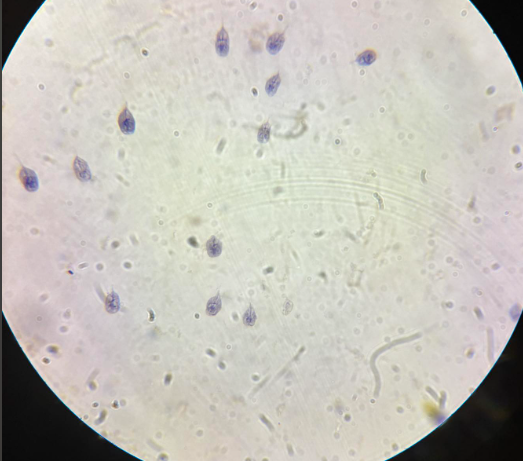

giardia intestinalis trofozoity

giardia intestinalis trofozoity